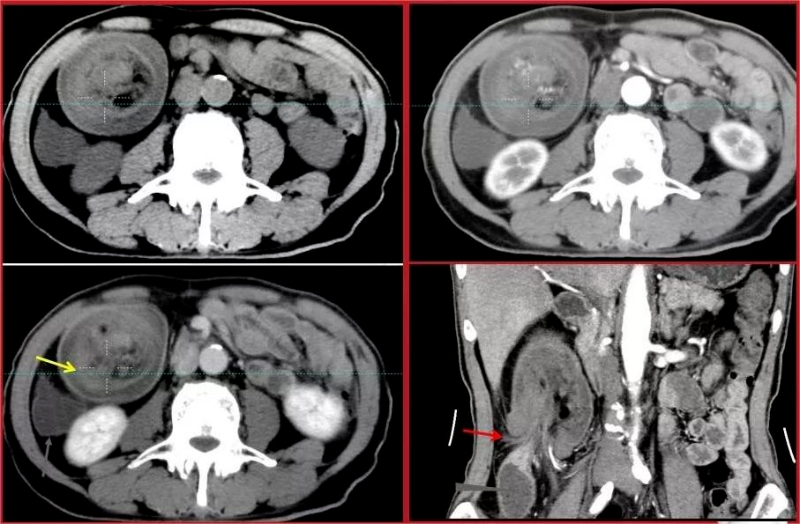

放射學檢查:如X光或CT掃描,可以幫助確定腸道是否有梗阻或套疊的跡象。

文章配圖